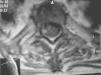

La tomografía computarizada (TC) de cráneo resultó normal. En la resonancia magnética (RM) se observó ensanchamiento medular, hiperintensidad homogénea intramedular en T1y T2, que se corroboró en los cortes axiales con imágenes heterogéneas y desplazamiento medular (figs. 1 y 2) y que se interpretó como hematoma espinal en fase de organización con datos de degeneración medular. Se suspendieron los anticoagulantes y se realizó una hemilaminectomía bilateral T2-T3, que evidenció un hematoma torácico en T2-T3 y un coágulo subdural en C4. El informe anatomopatológico mostró un hematoma antiguo parcialmente organizado y degeneración neuronal sin evidencia de neoplasia. La evolución de la paciente fue hacia la degeneración espinal, sin recuperación de la fuerza muscular ni del nivel sensitivo y sin actividad del LEG.

Entre los exámenes complementarios, la RM es superior a la TC. Los hallazgos típicos consisten en imágenes hiperintensas tanto en T1 como en T2, ensanchamiento medular, e incluso puede hacerse evidente una imagen de compresión medular. El tratamiento de la hemorragia intraespinal, más allá del tratamiento causal, deberá considerar las complicaciones de la mielopatía e intentar la evacuación quirúrgica lo más pronto posible9,11–14.